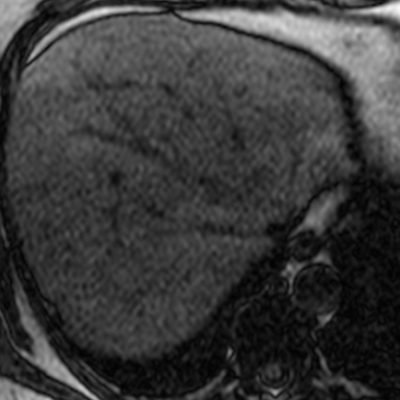

El estudio se complemento con resonancia magnética, donde se demostró la presencia de múltiples imágenes focales hepáticas confluentes con disminución de la señal en secuencias fuera de fase, no mostrando alteración de la señal en secuencias potenciadas en T2, sin signos de restricción al pulso difusión ni refuerzos anómalos luego de la administración de contraste endovenoso, estos hallazgos confirman la sospecha de esteatosis focal multinodular (fig. 5, 6 y 7).